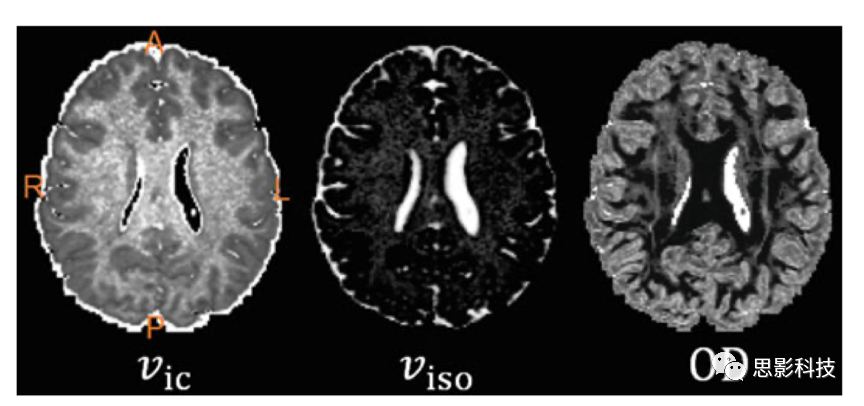

2)神經突方向散度和密度成像(neurite orientation dispersion and density imagingNODDI

NODDI方法主要對全腦神經突方向散度和密度進行成像??梢杂嬎?span>vic、viso、OD等標量指標進行進一步基于體素的統計分析。

圖例 NODDI指標